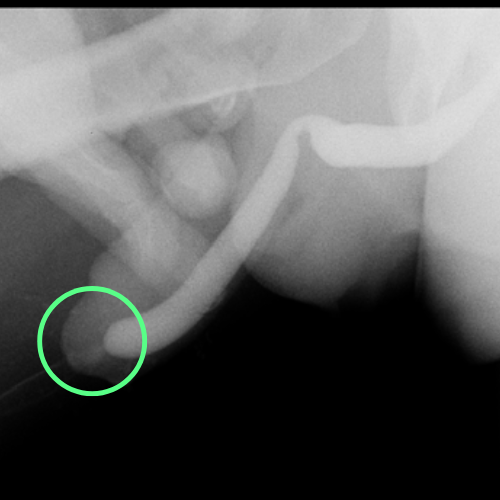

Cistouretrografía que revela estenosis de la uretra femenina

Estudio que muestra una estenosis de uretra (marcada con círculo) en una paciente mujer de una longitud considerable.

Cistouretrografía que muestra una estenosis del tercio distal de la uretra en una paciente mujer

Cistouretrografía que muestra una estenosis de uretra (marcada con círculo) en una paciente mujer, de una longitud menor que la anterior.